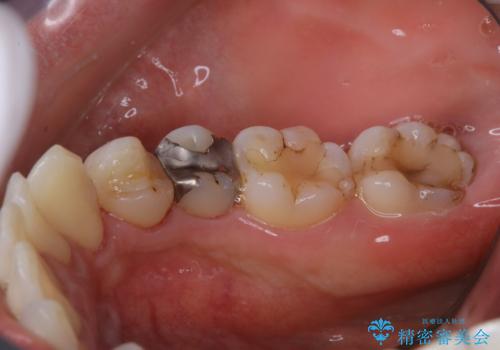

歯の表面に、茶色く色が残っている所がありますが、これは詰め物の変色によるものです。以前に、CR(コンポジットレジン)による虫歯治療がされています。

CRは経年的劣化や、着色してしまうことがあります。PMTCでクリーニングを行うと、古いCRが目立つことがあるため、気になる際は詰め替えを行います。

茶色くなっている部分が、着色なのか、劣化なのか、虫歯によるものなのかは判別が難しいことがあります。そのため、定期的にPMTCを行うことで状態の確認が的確に行えます。